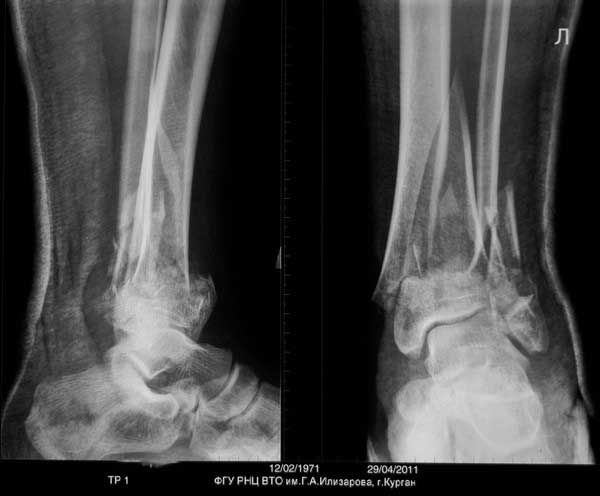

Выставляю случай не менее тяжелый. Фиксация в аппарате Мацукидиса-Шевцова 83 дня, общий срок нетрудоспособности 112 дней. Никаких проблем с остеосинтезом и с последующим лечением не было. Никаких воспалений мягких тканей. 3 перевязки за весь период лечения.Главное - захотеть.